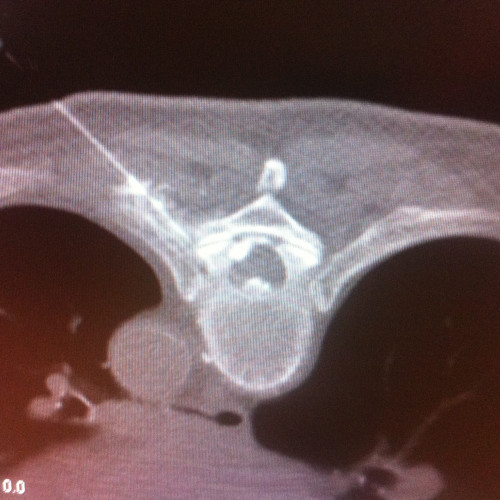

CT-gezielte Infiltrationsbehandlung – Es kann die Nadel millimetergenau an die betroffene Region gebracht werden. Die Strahlenbelastung ist in etwa gleich der röntgengezielten Infiltration mit dem Vorteil der besseren Darstellung der Strukturen. Die CT-gezielte Infiltration wird von mir im Röntgeninstitut „Bellaria Diagnose“ im ersten Wiener Bezirk ambulant durchgeführt.

- CT gezielte Infiltrationen der Facettengelenke, Nervenwurzeln, ISG, epidurale Flutungen caudal und dorsal